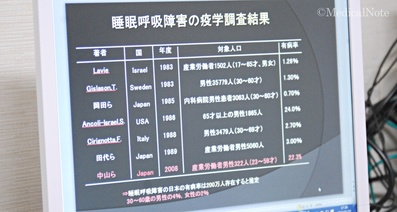

肺気腫とは、タバコの煙など有害物質が原因で、肺の組織が壊れた状態のことをいいます。40歳以上の男性が肺気腫になることが多く、特に60歳以上の男性が多いといわれています。

40歳以上の男性が肺気腫になることが多いのも、喫煙率と関係しています。男性は喫煙習慣のある方が多いため、肺気腫の患者さんが多いと考えられているのです。また、肺気腫はある一定の喫煙期間によって生じます。そのため、中高年から高齢にかけて肺気腫になることが多いと考えられます。たとえば、20歳代で喫煙を始めた方が40歳代や50歳代になって肺気腫になるイメージです。